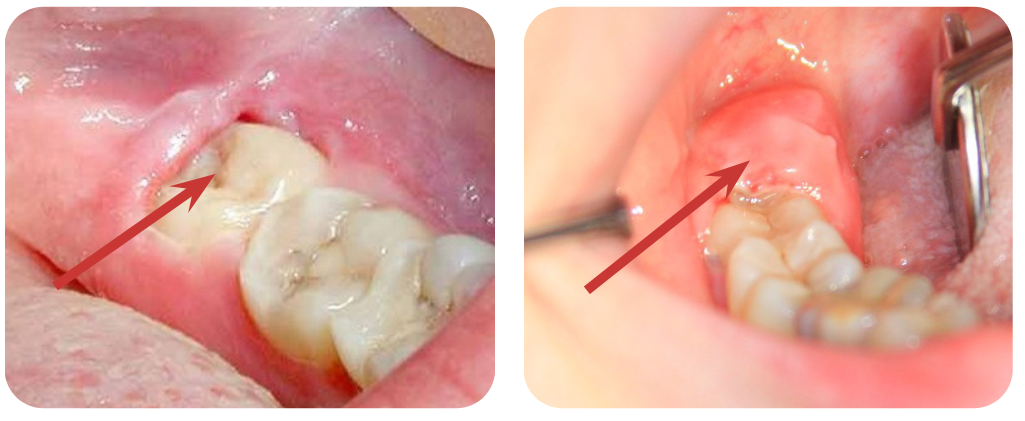

Знайте, что средние сроки прорезывания 8-х зубов — 18 - 29 лет, может чуть раньше, а может и позже. Самое безобидное, но чаще всего то, что приводит к врачу и это хорошо, если вос- паляется «капюшон» — слизистая оболочка над прорезающимся зубом. Если почувствовали дискомфорт (боль при прикосновении или смыкании зубов, отекла десна, больновато открывать рот) не терпите — идите к врачу. Да, может пройти, а может воспалиться снова и так не один раз, и не с одной стороны. Пусть врач оценит состояние зуба и, если проблема только с десной, проведет местное лечение, в крайнем случае иссечет слизистую, и на этом вопрос может быть закрыт.

Рис. 1. Восьмые зубы на обоих фото частично покрыты слизистой, которая воспалилась. Посещение врача должно состояться, как можно быстрее, чтобы воспалительный процесс не перешел на нижележащие мягкие ткани